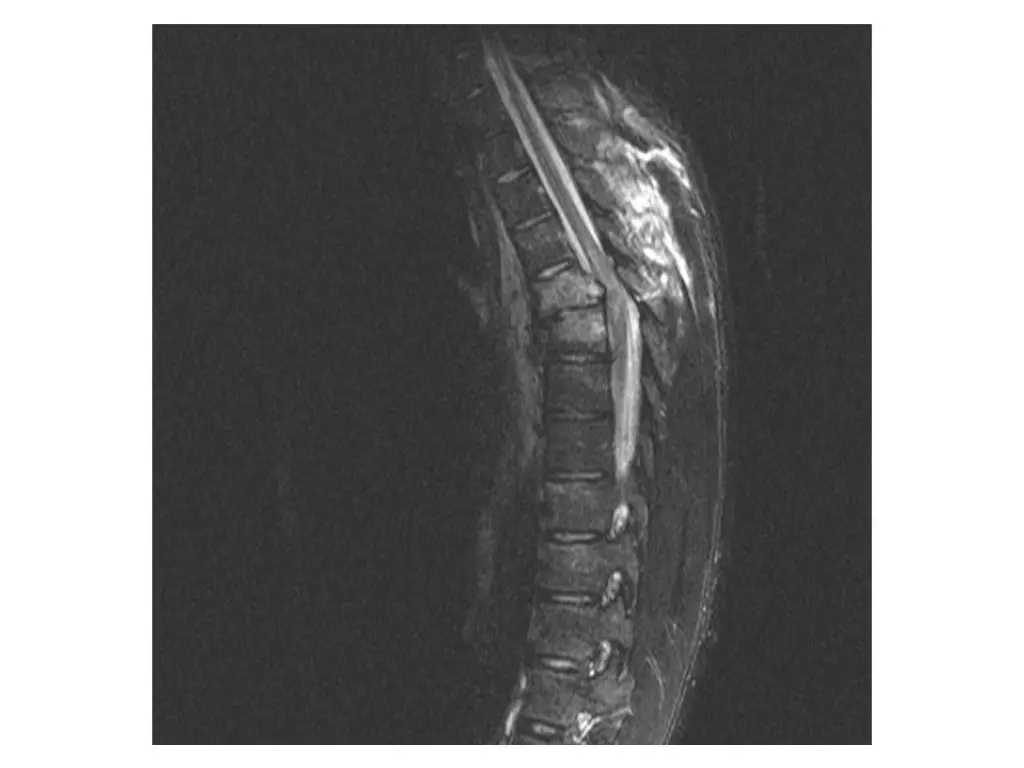

Clinical Hx (Case 1) 22 year old male. Ejected from a vehicle during a high speed single vehicle rollover. Immediate complaints of chest and back pain. Transported to FMC. Hemodynamically stable. No LoC. Injury to thoracic or lumbar spine and associated bilateral pulmonary contusions.

Neurological exam (Case 1) Upper extremity: Sensory: Normal to light touch and pinprick Motor: 5/5 power in all muscle groups Lower extremity: Sensory: Absent sensation Motor: 0/5 power in all muscle groups Rectal: Sensation: Absent Voluntary sphincter tone: Absent Other relevant findings: No sensation to pinprick below costal margin bilaterally. Complete absence of sensation below umbilicus.

Imaging (Case 1) Midsagittal CT scan Parasagittal CT scan Axial CT scan Midsagittal STIR MRI scan